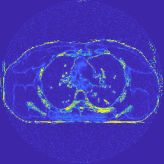

For a 3D cone-beam CT problem, circulant preconditioning is less accurate because the matrix is inherently shift-variant due to the system geometry and/or spatial variations in detector response [44]. Despite this fact, we select a circulant preconditioner to approximate in (4), and solve (2) in 3D CT reconstruction using more PCG inner iterations. The reason is three fold. First, a circulant preconditioner is still one of the classical options to approximate a shift-variant matrix (e.g., ) and accelerate CG (see, for example, [44, 45]). Second, effective learned transforms are generally close to orthogonal (the same applies to the 2D case), and a scaled identity preconditioner can approximate the term . Third, a few PCG iterations in Algorithm 1 can provide fast convergence: 1) Fig. 2 shows that and PCG iterations give very similar convergence rates; 2) in the 3D CT reconstruction, the convergence rates of Algorithm 1 are comparable to those provided in 2D CT reconstruction – see Fig. 5. More sophisticated preconditioners might provide faster convergence [46, 47].

III-B2 Algorithm Convergence Rate

Our main concern in convergence rates of Algorithm 1 lies with an inaccurate preconditioner (e.g., circulant one) particularly for the 3D sparse-view CT reconstructions. To see the effects of using a loose preconditioner in Algorithm 1, we compared the convergence rates of the 3D case with those of 2D (Fig. 5(a) and Fig. 5(b)). In the first iterations, Algorithm 1 converges faster in 2D experiments than 3D experiments. However, after iterations, the convergence rates of Algorithm 1 are similar in both 2D and 3D reconstructions. In addition, more PCG (with a circulant preconditioner) iterations does not significantly accelerate Algorithm 1 (see Fig 2). These empirically observations imply that, in the 3D sparse-view CT reconstructions, Algorithm 1 using a circulant preconditioner ( PCG iterations) is a reasonable choice.